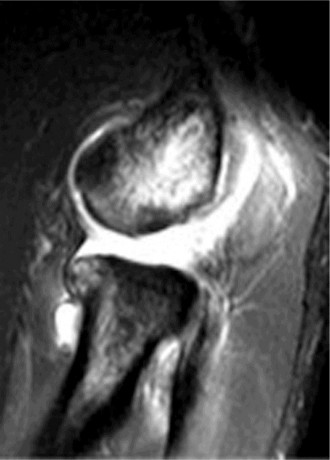

Treat a patient with scapular winging? CASE 23 A 47-year-old, right-hand-dominant male presents to your clinic complaining of right shoulder weakness for the past 2 months. He denies any history of trauma but notes sudden onset of pain 2 months ago that lasted approximately 2 weeks and then subsided without any intervention and was followed by shoulder weakness. He works as a lawyer and has been going through a divorce for the past year. Physical examination reveals no tenderness to palpation about the shoulder. He has decreased sensation over the lateral aspect of the shoulder, decreased muscle bulk over the left shoulder compared with the contralateral side, and weakness with left shoulder abduction. He is distally neurovascularly intact. The patient had already been referred for an x-ray and MRI by his primary care doctor that are shown in Figures 2–62 and 2–63.

Figure 2–62

Figure 2–63

The correct answer is (C). The patient’s decreased sensation over the deltoid, deltoid muscle atrophy on examination, and MRI with atrophy of the teres minor points to axillary nerve dysfunction. Suprascapular nerve injury (Choice A) would result in atrophy of the infraspinatus and or infraspinatus muscles, leading to weakness with external rotation and/or forward flexion. Dorsal scapular nerve injury (Choice B) would result in weakness of the rhomboid muscles and levator scapulae. While injury to the posterior cord of the brachial plexus (Choice D) would result in symptoms of axillary nerve palsy, they would also involve dysfunction of the radial nerve, which also comes off the posterior cord.

The correct answer is (B). Parsonage Turner syndrome (brachial neuritis) is characterized by acute brachial neuropathy which can affect different nerves of the brachial plexus. In this patient, it is the most likely explanation for his atraumatic deltoid paralysis with axillary nerve palsy in a time of severe stress. The cause of Parsonage Turner Syndrome is unknown, but it has been associated with severe stress and viral infection. Quadrilateral space syndrome (Choice A) involves entrapment of the axillary nerve as it passes through the quadrilateral space, would present as chronic dull pain, and is usually not associated with decreased sensation. While Choices C and D can both be a cause of axillary nerve injury, the patient has no history of trauma and there are no masses on his MRI.